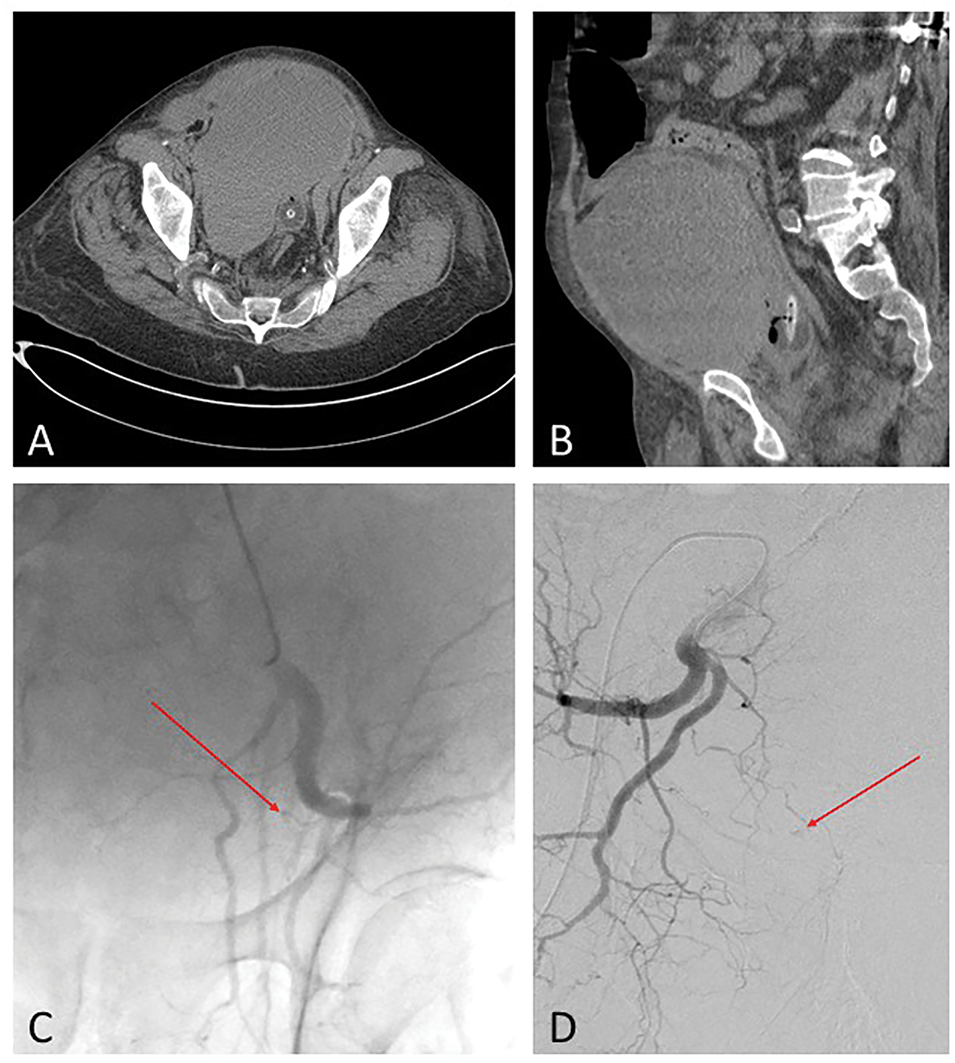

The patient was initially admitted for respiratory distress secondary to COVID-19, managed with oxygen therapy. During his hospital admission, the patient became hemodynamically unstable, and further evaluation with axial imaging studies confirmed an expanding pelvic hematoma (Figure 1A,B) with supratherapeutic international normalized ratio (INR) up to 10.6. The patient had intermittent episodes of hypotension (systolic blood pressure between 70–80 mmHg) that were responsive to fluid resuscitation. His hemoglobin levels had decreased from 11.9 g/dL on presentation to 8.4 g/dL. A CT-angiogram of the abdomen and pelvis showed active arterial extravasation associated with a spontaneously enlarging pelvic hematoma without any preceding pelvic trauma. Active extravasation from right and left internal iliac arterial branches was confirmed in angiogram (Figure 1C,D) and managed successfully by angioembolization using Gelfoam slurry.

FIGURE 1. Pelvic computerized tomography (CT) scan of the large expanding pelvic hematoma in a patient with supratherapeutic international normalized ratio (INR) up to 10.6. (A) Axial; (B) Sagittal view. Active extravasation (Arrows) from (C) left and (D) right internal iliac arterial branches was confirmed in angiogram